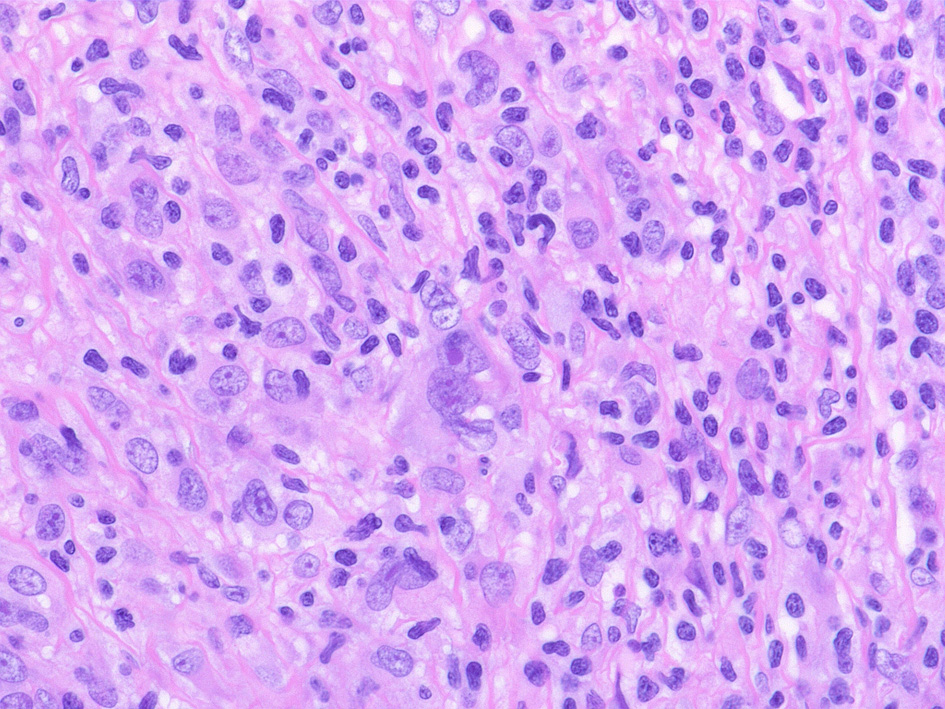

48歳男性 頚部リンパ節 Hodgkin lymphoma, mixed cellular type.

Hodgkin cell, Reed-Sternberg cells

左;腫瘍細胞のクラスター, 右: mummy cell-ミイラ細胞

古典的/診断価値のあるHRS細胞のプロトタイプはこの病型でみられ核小体のサイズは周囲小型リンパ球核と同等かそれ以上であり「Owl-eye」と呼ばれる。程度は軽いがlacunar現象の見られることがある。

背景にはリンパ球, 形質細胞, 好酸球, 組織球などがみられ、いずれかが優位な場合もある。組織球はしばしば類上皮様となり特にEBV感染例にみられ肉腫様組織像を形成することがある。